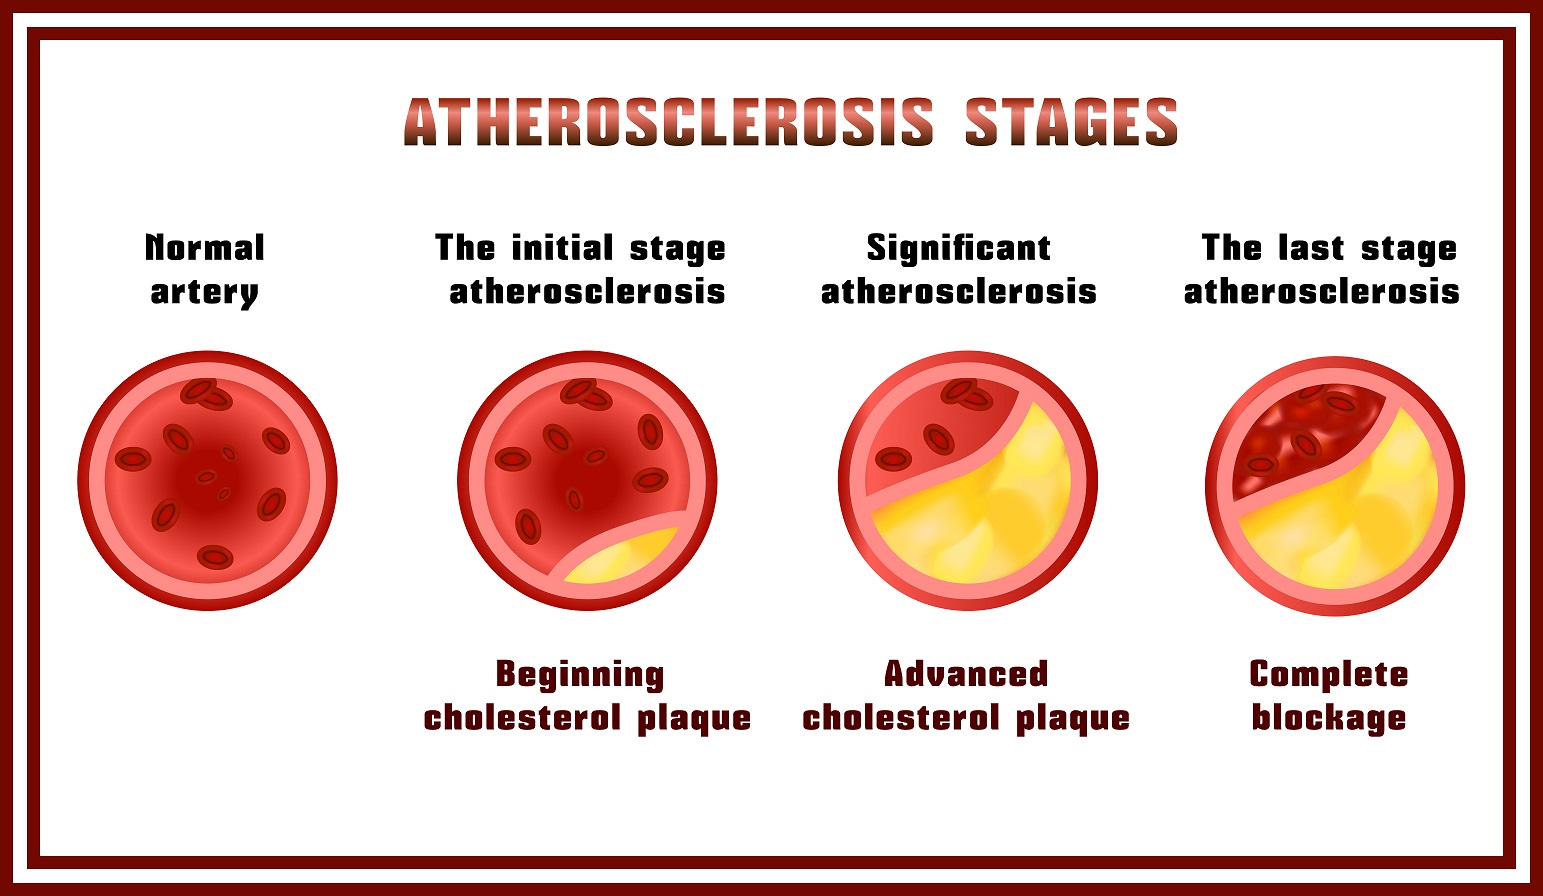

Všeobecne sa jedná o všetky ochorenia srdca, ale v užšom meradle sa bavíme o chorobách, ktoré sú spôsobené aterosklerotickými degeneratívnymi zmenami. Presne ide o choroby: ischemická choroba srdca (ICHS, vedie k infarktu myokardu), ischemická choroba dolných končatín (PAOD) a ischemická cievna mozgová príhoda (ICMP, mŕtvica). Všetky sú spôsobené upchatím niektorej tepny (choroba sa nazýva podľa toho, kde sa daná tepna nachádza) aterosklerózou. Tepna sa upchá aterosklerotickým plátom, ktorý sa skladá z tukov, ktorý sa v priebehu rokov ukladá viac a viac, znemožňuje priechod krvi, až sa prietok zastaví úplne. Jednotlivé choroby môžu mať ale aj iné príčiny, napr. Krvné zrazeniny, bublinky vzduchu alebo vaskulitída (zápalové ochorenie ciev).